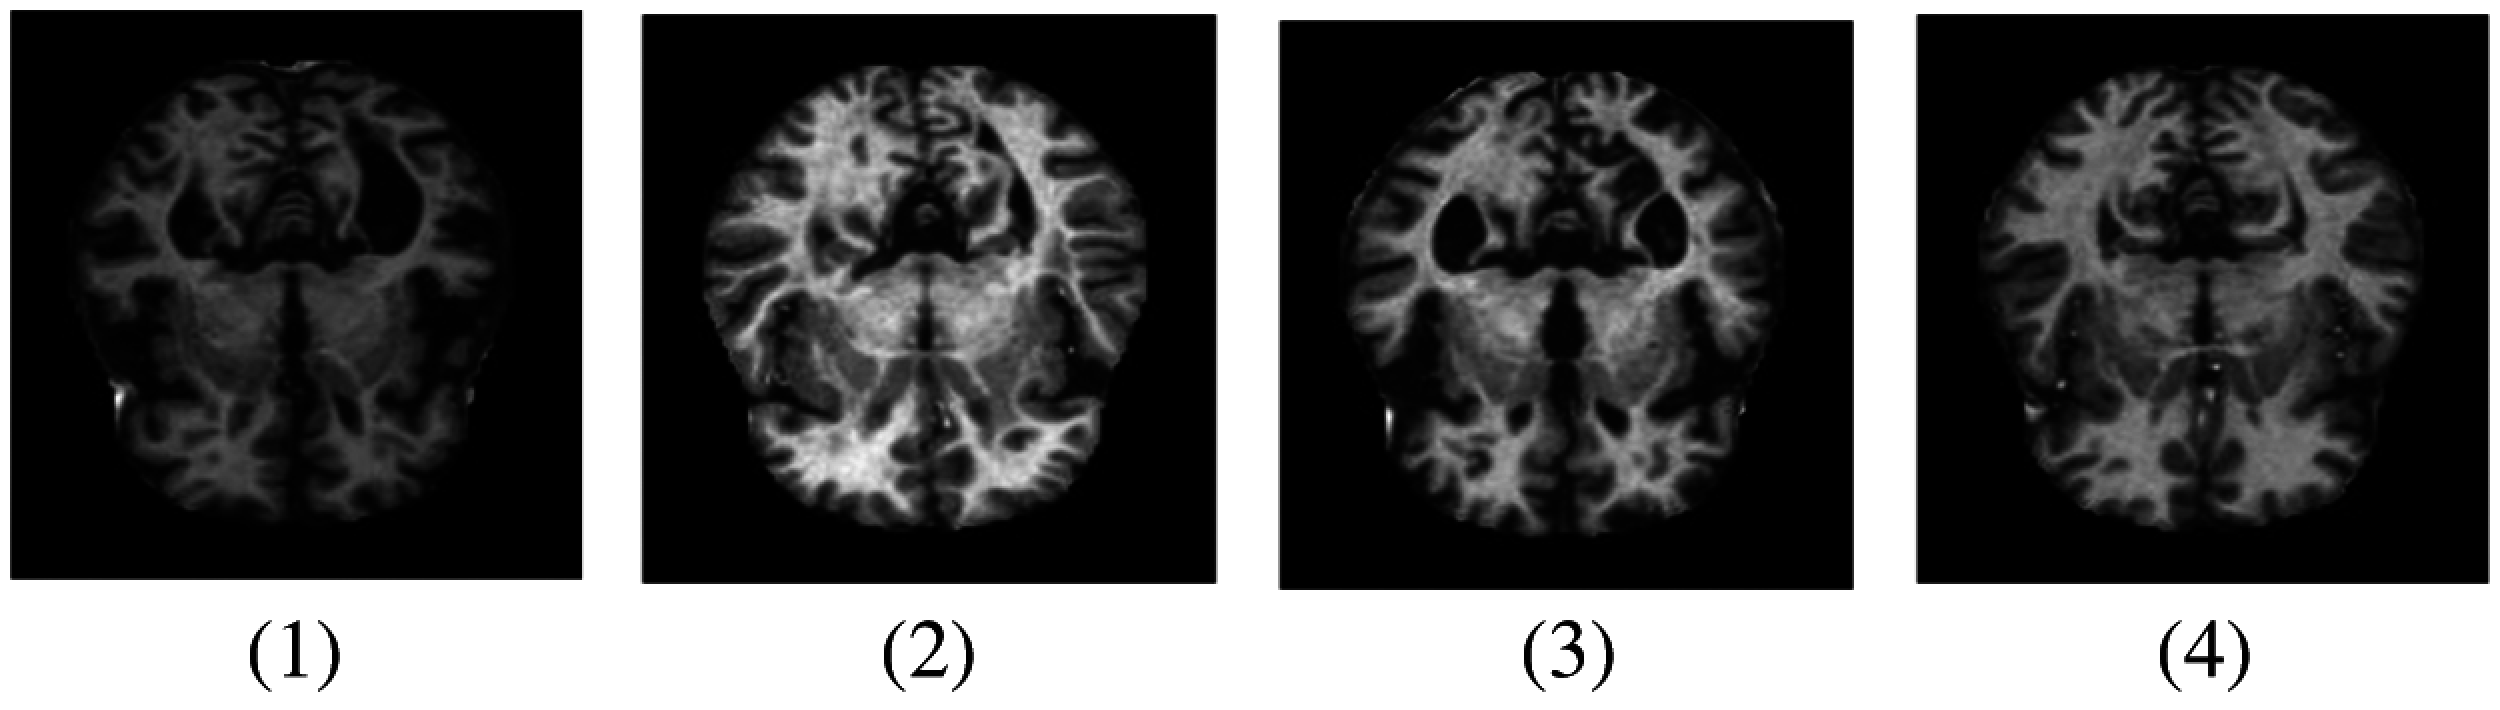

Deep learning and machine learning models have been effectively implemented in various fields of medical image analysis such as Mammography, Ultrasound, Microscopy, MRI, etc. [7]. Deep learning models show a significant result in several disease classifications and detections like heart, lung, brain, retina, breast, bone, etc. These models have shown prominent results in various medical fields, but little work has been done in AD detection. MRI data can be used to detect the early detection of AD which can help medical consultants to restrain the speed of disease in the brain [8]. In our research work, we have used an MRI dataset for the classification and detection of AD with a deep learning model. The sample images are shown in Fig. 1.

Figure 1: Samples of MRI images representing different AD stages. (1) MD; (2) MOD; (3) ND; (4) VMD